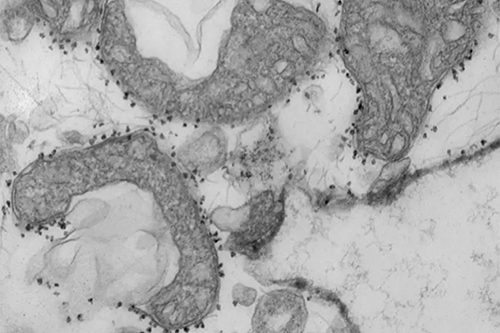

ÏßÁ£ÌåDNAˮƽÊÇ×éÖ¯ËðÉ˵ÄÁ¿¶È¡£Í¼Îª´ÓÈË·ÎÊͷŵÄÊÜËðÏßÁ£Ì壨Éî»ÒÉ«ÇøÓò£©¡£ÏßÁ£ÌåÖÜΧµÄСºÚµãÊÇ´ÅÐÔÖé×Ó£¬ÉÏÃæ´øÓп¹Ì壬ÕâЩ¿¹ÌåÓÃÓÚ¸ôÀëºÍÑо¿ÒÑ´ÓÃÖÁôµÄ×éÖ¯ÖÐÊͷųöÀ´µÄ²»¿µ½¡µÄÏßÁ£Ìå¡£